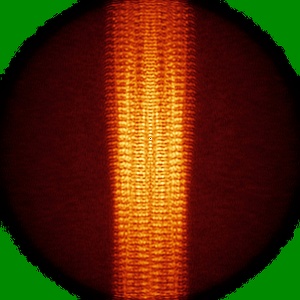

Tropomyosin-receptor kinase fused gene protein (TRK-fused gene protein; TFG) Low Complexity Domain (residues 237-327) P285L mutant, amyloid fiber

Helical reconstruction2.59 Å

Sample: amyloid fibril of protein TFG P285L

Fibril structures of TFG protein mutants validate the identification of TFG as a disease-related amyloid protein by the IMPAcT method.